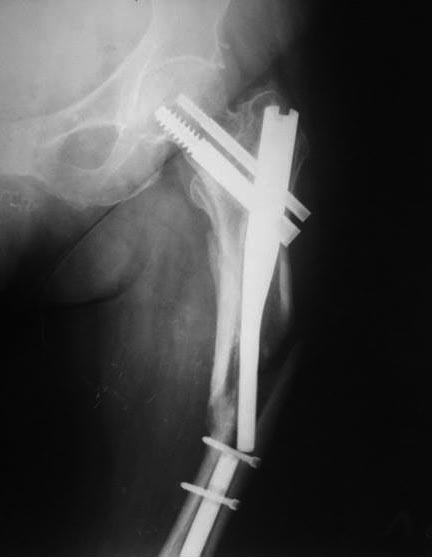

Перелом PFN

Добрый день, уважаемые коллеги. Пациентка Т. 79 лет травма 11 мес. После операции передвигалась при помощи костылей с дозированной нагрузкой.

Со слов, через месяц после операции появилась боль в области перелома, за мед помощи не обращалась. Сопутствующая патология бронхиальная астма ( на гормонах)

Хорошая иллюстрация того, что стандартную версию PFN нельзя использовать при локализации перелома ниже уровня малого вертела.

Нужно было гвоздь для диафизарных переломов ставить. Медиальной опоры нет, гвоздь короткий, перегрузка по каналу для винта и закономерный перелом импланта.